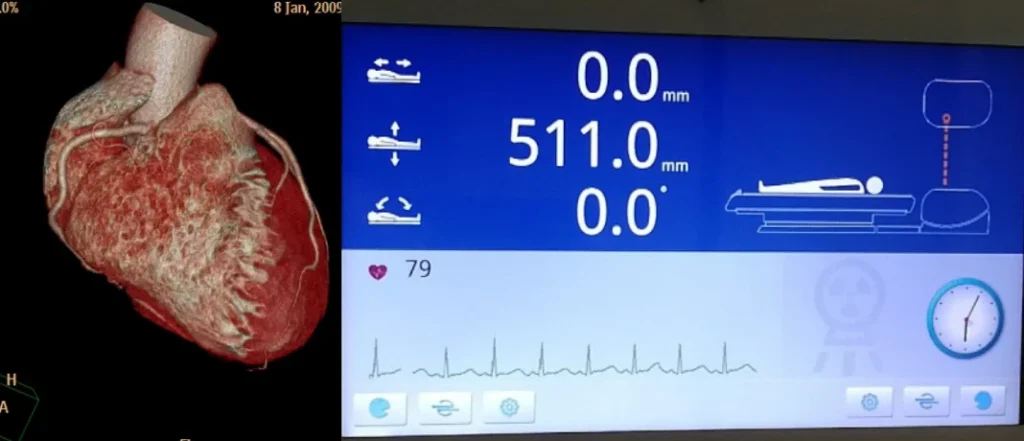

HERZ-SCANNING:

• Prospektives EKG-Scanning: Unterstützt

• Retrospektives EKG-Scanning: Unterstützt

• Mehrsektor-Koronararterien-Scanning

: Auto-adaptiver Sektor mit

maximal 4 Sektoren.

• Zeitliche Auflösung: 60 ms; 25 ms @RTF

• EKG-Wellenformbearbeitung:

Funktionen zum Bearbeiten, Hinzufügen und Löschen

abnormaler EKGs (z. B. Extrasystolen)

zur Koronararterien-Erkennung

.

• Herzrekonstruktion: Automatische Auswahl der optimalen

Erkennungsphase ; mehrphasige Erkennung für ein einzelnes Bild.

• Echtzeit-Fokus- Technologie (RTF) zur sofortigen Koronararterienvereisung • Der auf Deep Learning basierende

Bewegungsartefaktkorrekturalgorithmus

der dritten Generation

modelliert und kompensiert

Herzbewegungsartefakte und

eliminiert teilweise Artefakte, die durch

unzureichende Bewegung, Atmung und zeitliche Auflösung verursacht werden

. Bewegungsabweichungen werden

iterativ korrigiert.

• Verfahren zur Vermeidung von Überkorrektur.

128-Zeilen-CT: Entwickelt für

Herzuntersuchungen

» Schneller 0,25-Sekunden-Herzscan

» EKG im Gantry integriert »

46 ms zeitliche Auflösung des Herzens »

Prospektive oder retrospektive Eingabe mit

bis zu vier Sektoren